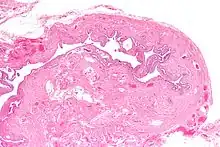

| Micrograph of salpingitis isthmica nodosa, showing the characteristic nodular thickening. H&E stain. | |

Salpingitis isthmica nodosa (SIN), also known as diverticulosis of the fallopian tube, is nodular thickening of the narrow part of the uterine tube, due to inflammation.

It is characterized by nodular thickening of the tunica muscularis of the narrow (isthmic) portion of the fallopian tube. In severe cases, it leads to complete obliteration of the tubal lumen. It is uncommonly bilateral.[2]

Microscopic findings:

- Glandular epithelium within tubal muscularis propria, in continuation with mucosa or (more commonly) discontinuous

- Haphazard distribution (akin to adenomyosis) or pseudoinfiltrative

- Banal epithelium with tubal differentiation[4]